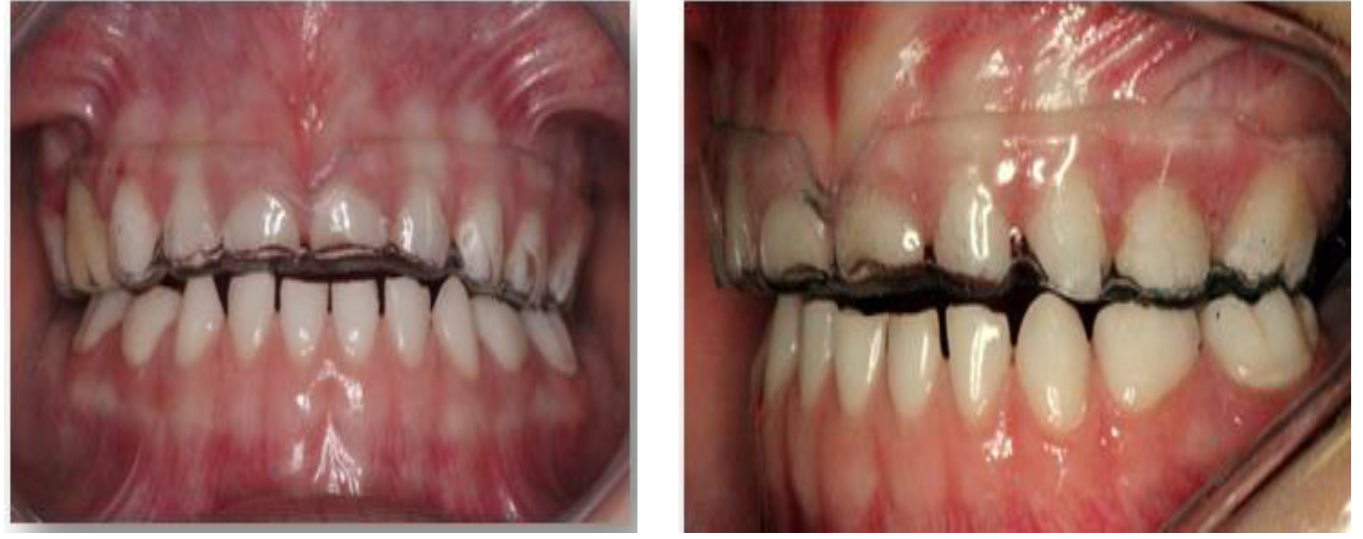

Dentro de las señales clínicas están relacionadas con asimetrías faciales, debilidad labial, respiración bucal, lesiones en la mucosa bucal, denticiones en el borde lateral de la lengua, mordida cruzada anterior y posterior, desgastes de las estructuras de soporte de los dientes, (desgastes lisos, rechinamiento y desgastes rugosos, apretamiento), ensanchamiento de la lamina dura, fracturas dentarias o de restauraciones, incremento de la línea alba, formación de trincas o facetas en los dientes, erosiones cervicales en los dientes, problemas periodontales, mobilidad dentaria, desarrollo de una falsa clase III, aceleración del proceso de rizólisis en dientes deciduos, alteración en la cronología de erupción de dientes permanentes y apiñamiento dental. Por otro lado, en relación a los síntomas relacionados al bruxismo se encuentran: hipersensibilidad pulpar, dolores de cabeza, hipertrofia y dolor a la palpación de los músculos masticadores (masetero, temporal y pterigoideo lateral), dolores y disturbios en la ATM, dolores al abrir o masticar.

Evaluación de los movimientos mandibulares, con presencia de desvió de línea media, con abertura máxima de 43 mm y lateralidad izquierda de 7 mm, sin presencia de overjet u overbite.

En la evaluación dentaria, se observa ausencia de la pieza 54, sin presencia de overjet y overbite, con clase I molar y caninos y desvío de línea media.

Figura 14. Ajuste oclusal bilateral para establecer puntos de contactos estables y equilibrados. Después de realizar los controles oclusales y la instalación de la placa se realizaron controles pos-instalación a los 15,30,60 y 90 días.